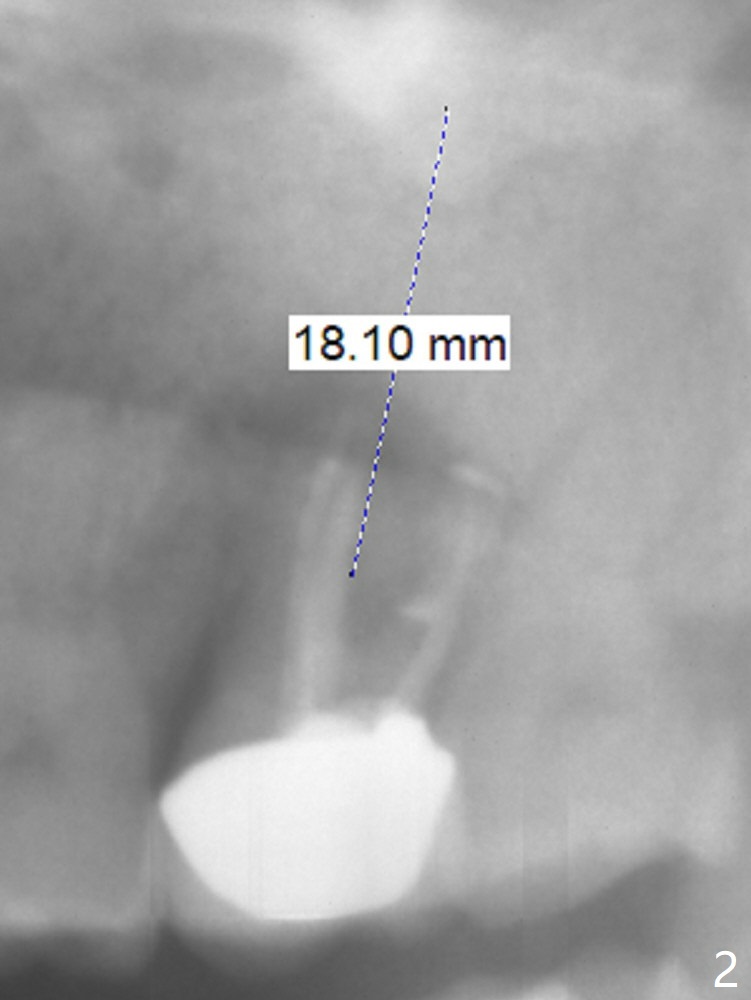

A 59-year-old man had large caries at the tooth #15 in 2009 (Fig.1). There is sign of root fracture in 2014 post RCT (Fig.2, unilateral mastication: #31 missing). Now the affected tooth turns into residual roots with #16 mesial shift (reduced mesiodistal dimension at the edentulous area). A long, relatively narrow implant is to be prepared (Fig.1,2). Take PA preop to confirm that radiolucency is reduced after tooth fracture and residual root coronal displacement.